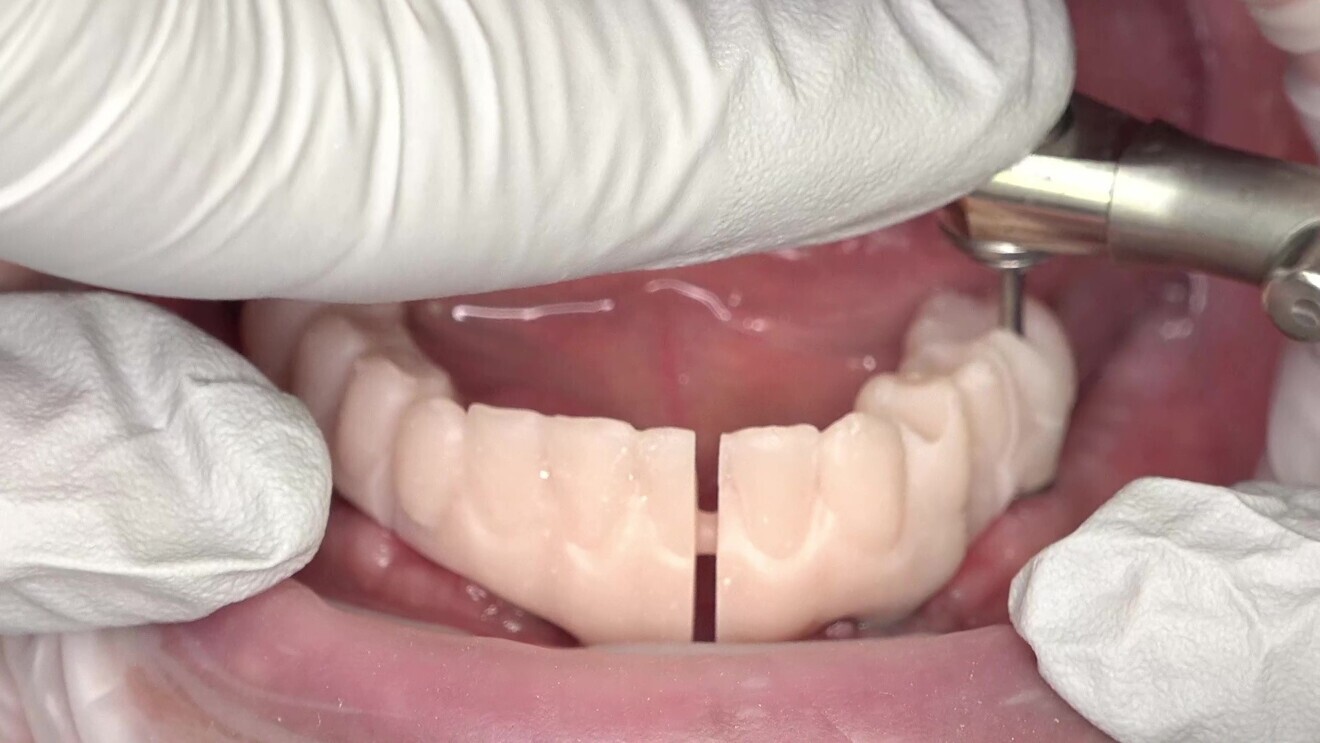

The second set of try-ins was used to check various factors, including aesthetics, occlusion, bite height, hygiene capability, phonetics and function. One important consideration is to avoid using the OptraGate retractor (Ivoclar) when checking the bite. The retractor affects muscular activity and could negatively impact the validation process. These final try-ins closely resembled the final prostheses and were used to make any necessary adjustments before fabricating the final prostheses (Figs. 11 & 12).

In this case, the validator did not break, and we did not need to make any changes to the validator. If a fracture is present, the practitioner needs to identify and locate the source of the misfit. He or she should then attach the broken segments with composite, remove the validator and sent it back to the laboratory for precision scanning. If the operator has to change the occlusion or adjust anything on the try-in, a new intra-oral scan will have to be taken so that the technician can adjust accordingly.

Fig. 14: Try-in of the lower jaw prosthesis.